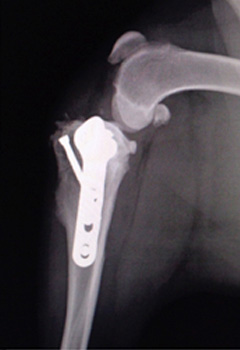

▲手術後のX線写真